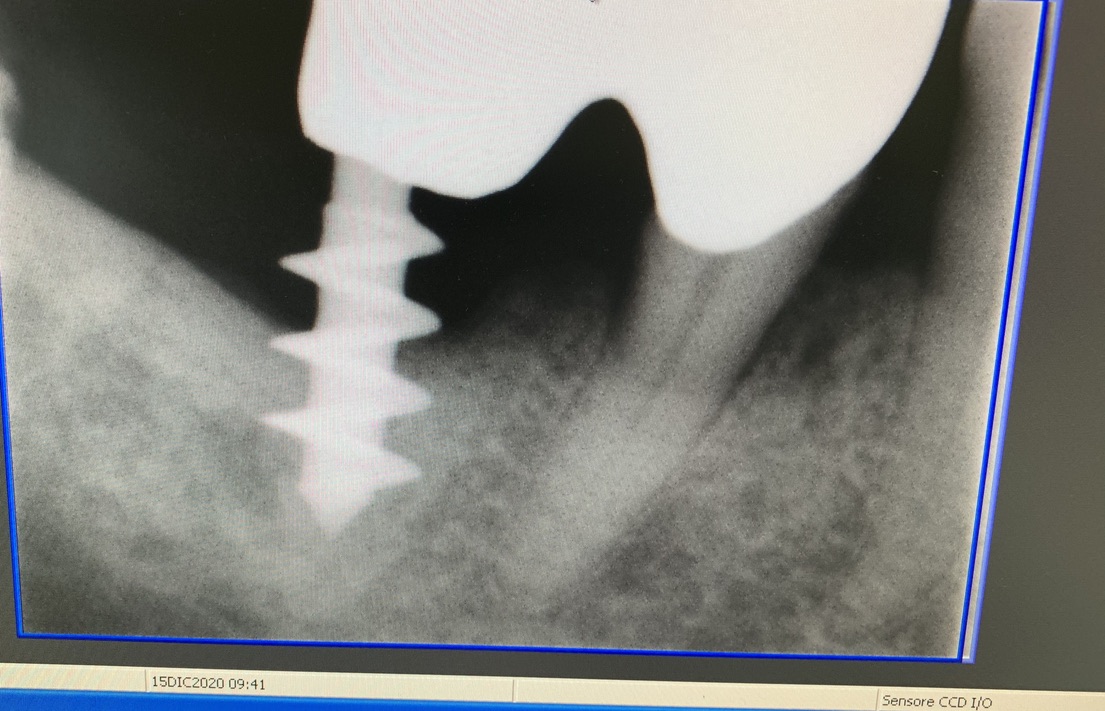

Original form of the Tramonte implant. 5 mm diameter with 3 threads. Stem diam. 2.1 mm. Neck diam. 2 mm x 5 mm in length. Grade 2 titanium. Grade 2 allowed the need to bend the implant neck to improve parallelism. It is an immediate post-extraction implant. Therefore, in the same session, extraction, boring, tapping and implant insertion. Immediately followed by monconization and the preparation of temporary crowns in light occlusion. The radiographs provided show the situation since 2010. The emergence of the thin neck favors the formation of a dense gingiva sleeve that protects against peri implantitis. The wide threads radiate the occlusal load away from the implant body, favoring the formation of a more homogeneous bone.